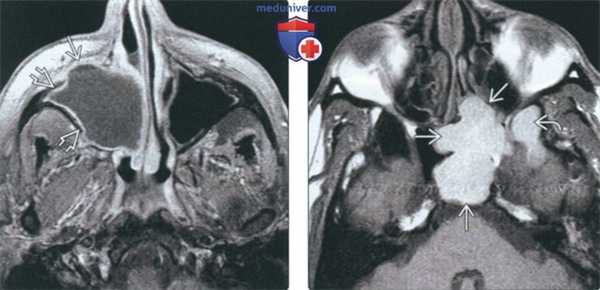

(Слева) На аксиальной МРТ (Т1 ВИ С+ FS) определяется мукоцеле правой верхнечелюстной пазухи с эрозией передней стенки и распроаранением в полость носа. Слизиаая оболочка на периферии накапливает контраст, что помогает отличить мукоцеле от новообразования.

(Справа) На аксиальной МРТ (Т1 ВИ) определяется большое мукоцеле правой сфеноидальной пазухи с однородным гиперинтенсивным сигналом, обусловленным большим содержанием белка. Обратите внимание на вовлечение бокового кармана.